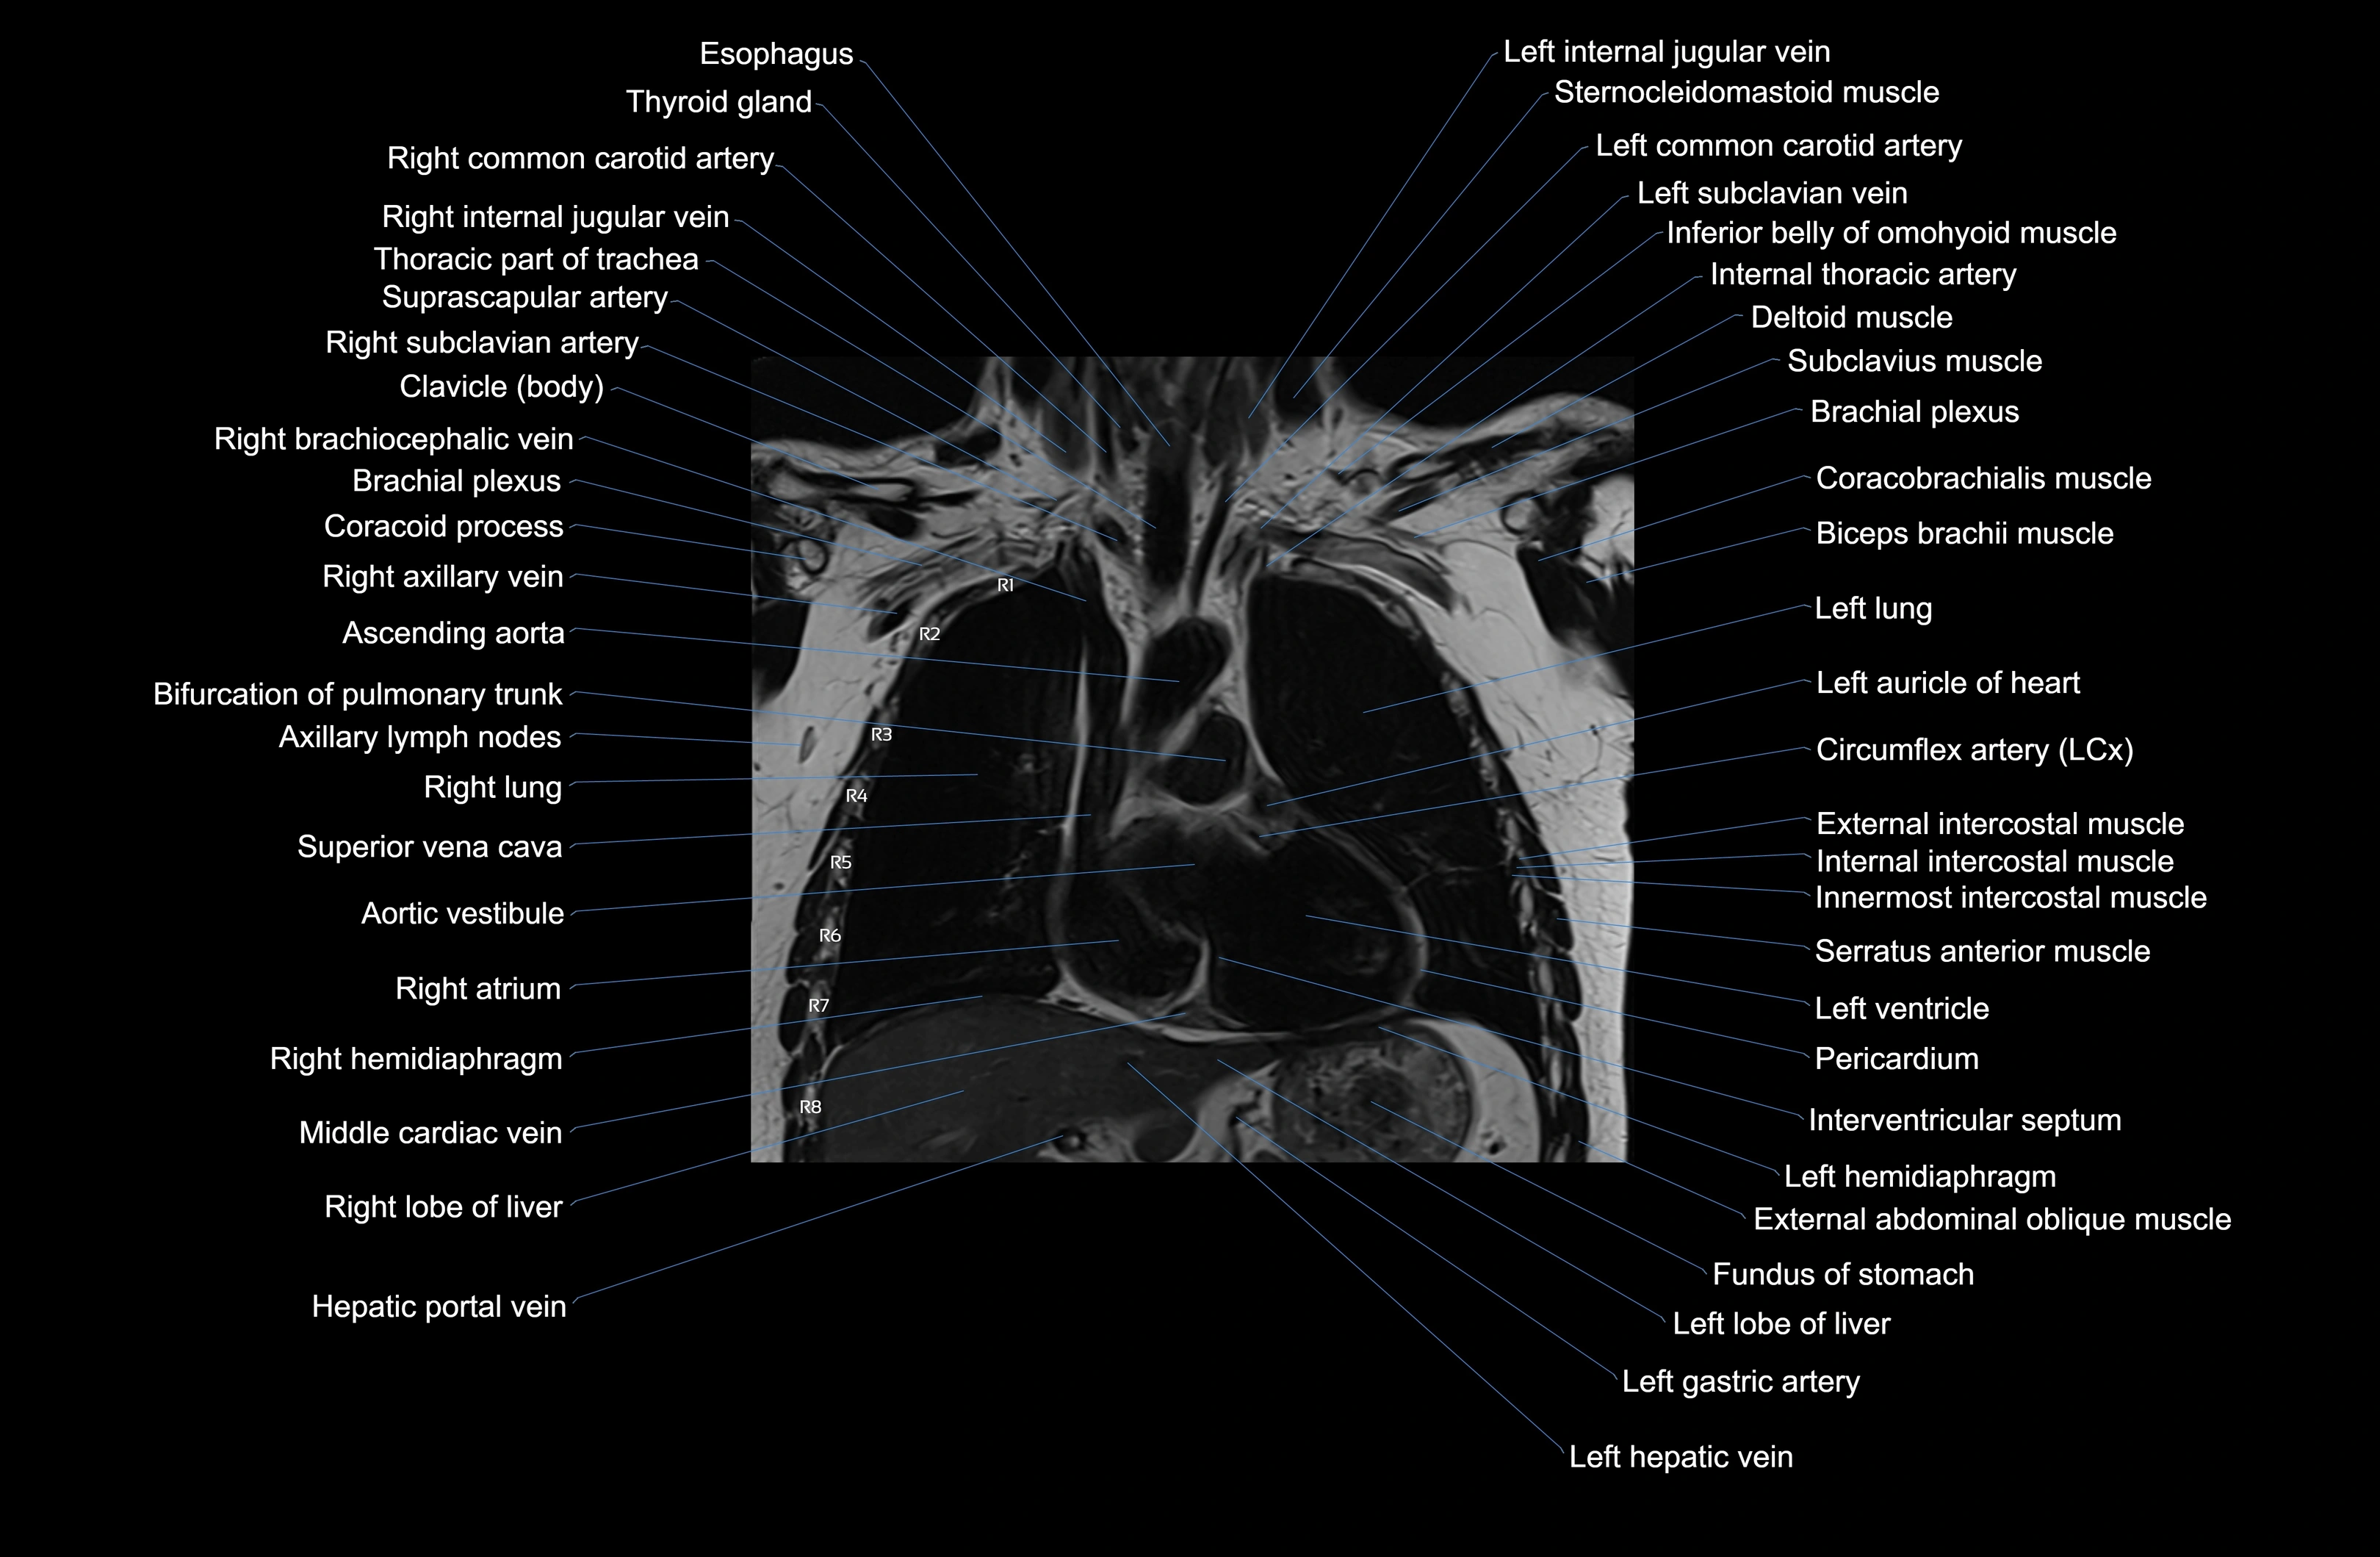

- T (Thoracic spine)